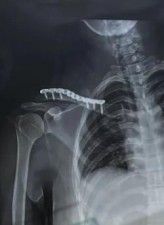

Большинство переломов могут быть диагностированы с помощью простых антеропостериальных рентгенограмм. Рентгенограммы наклона головки 20 ° устраняют влияние перекрывающихся грудных полостей. Пациенты должны быть рентгенограмма в положении самоподдерживания, чтобы лучше визуализировать смещение переломов. Веса для рентгенограммы помогает в оценке целостности ростральной клавикулярной связки в дистальной ключице или акромиоклавикулярной повреждениях суставов. Взятие рентгенограммы грудной клетки помогает исключить связанную торакальную травму, а укорочение может быть оценено путем сравнения с контралатеральной ключицей, а также исключая лопатологическую стенку.

3.5 Систематические сжатые пластины, реконструкционные пластины или пластиковые LCP могут использоваться для закрепления переломов ключицы. Пластины плавно расположены над или передней к ключице. Пластины более сильнее в биомеханических травмах, когда они расположены превосходно, особенно если внизу есть разбитый перелом, и их проще в визуализации. Необходима бикортикальная фиксация винтов, и отверстия должны быть просверлены с большой осторожностью, так как внизу риск повреждения нервов и кровеносных сосудов. Преимущества: безопасное бурение переднего винтового канала, приложение пластины, легкая контур.

Выбор имплантатов пластин зависит от размера бокового костяного блока. Для бокового костяного блока требуется минимум 3 бикортикальных винта. В идеале, винты натяжения должны использоваться для наклонных переломов. Если костный блок слишком мал для фиксации, может использоваться крючка ключица.